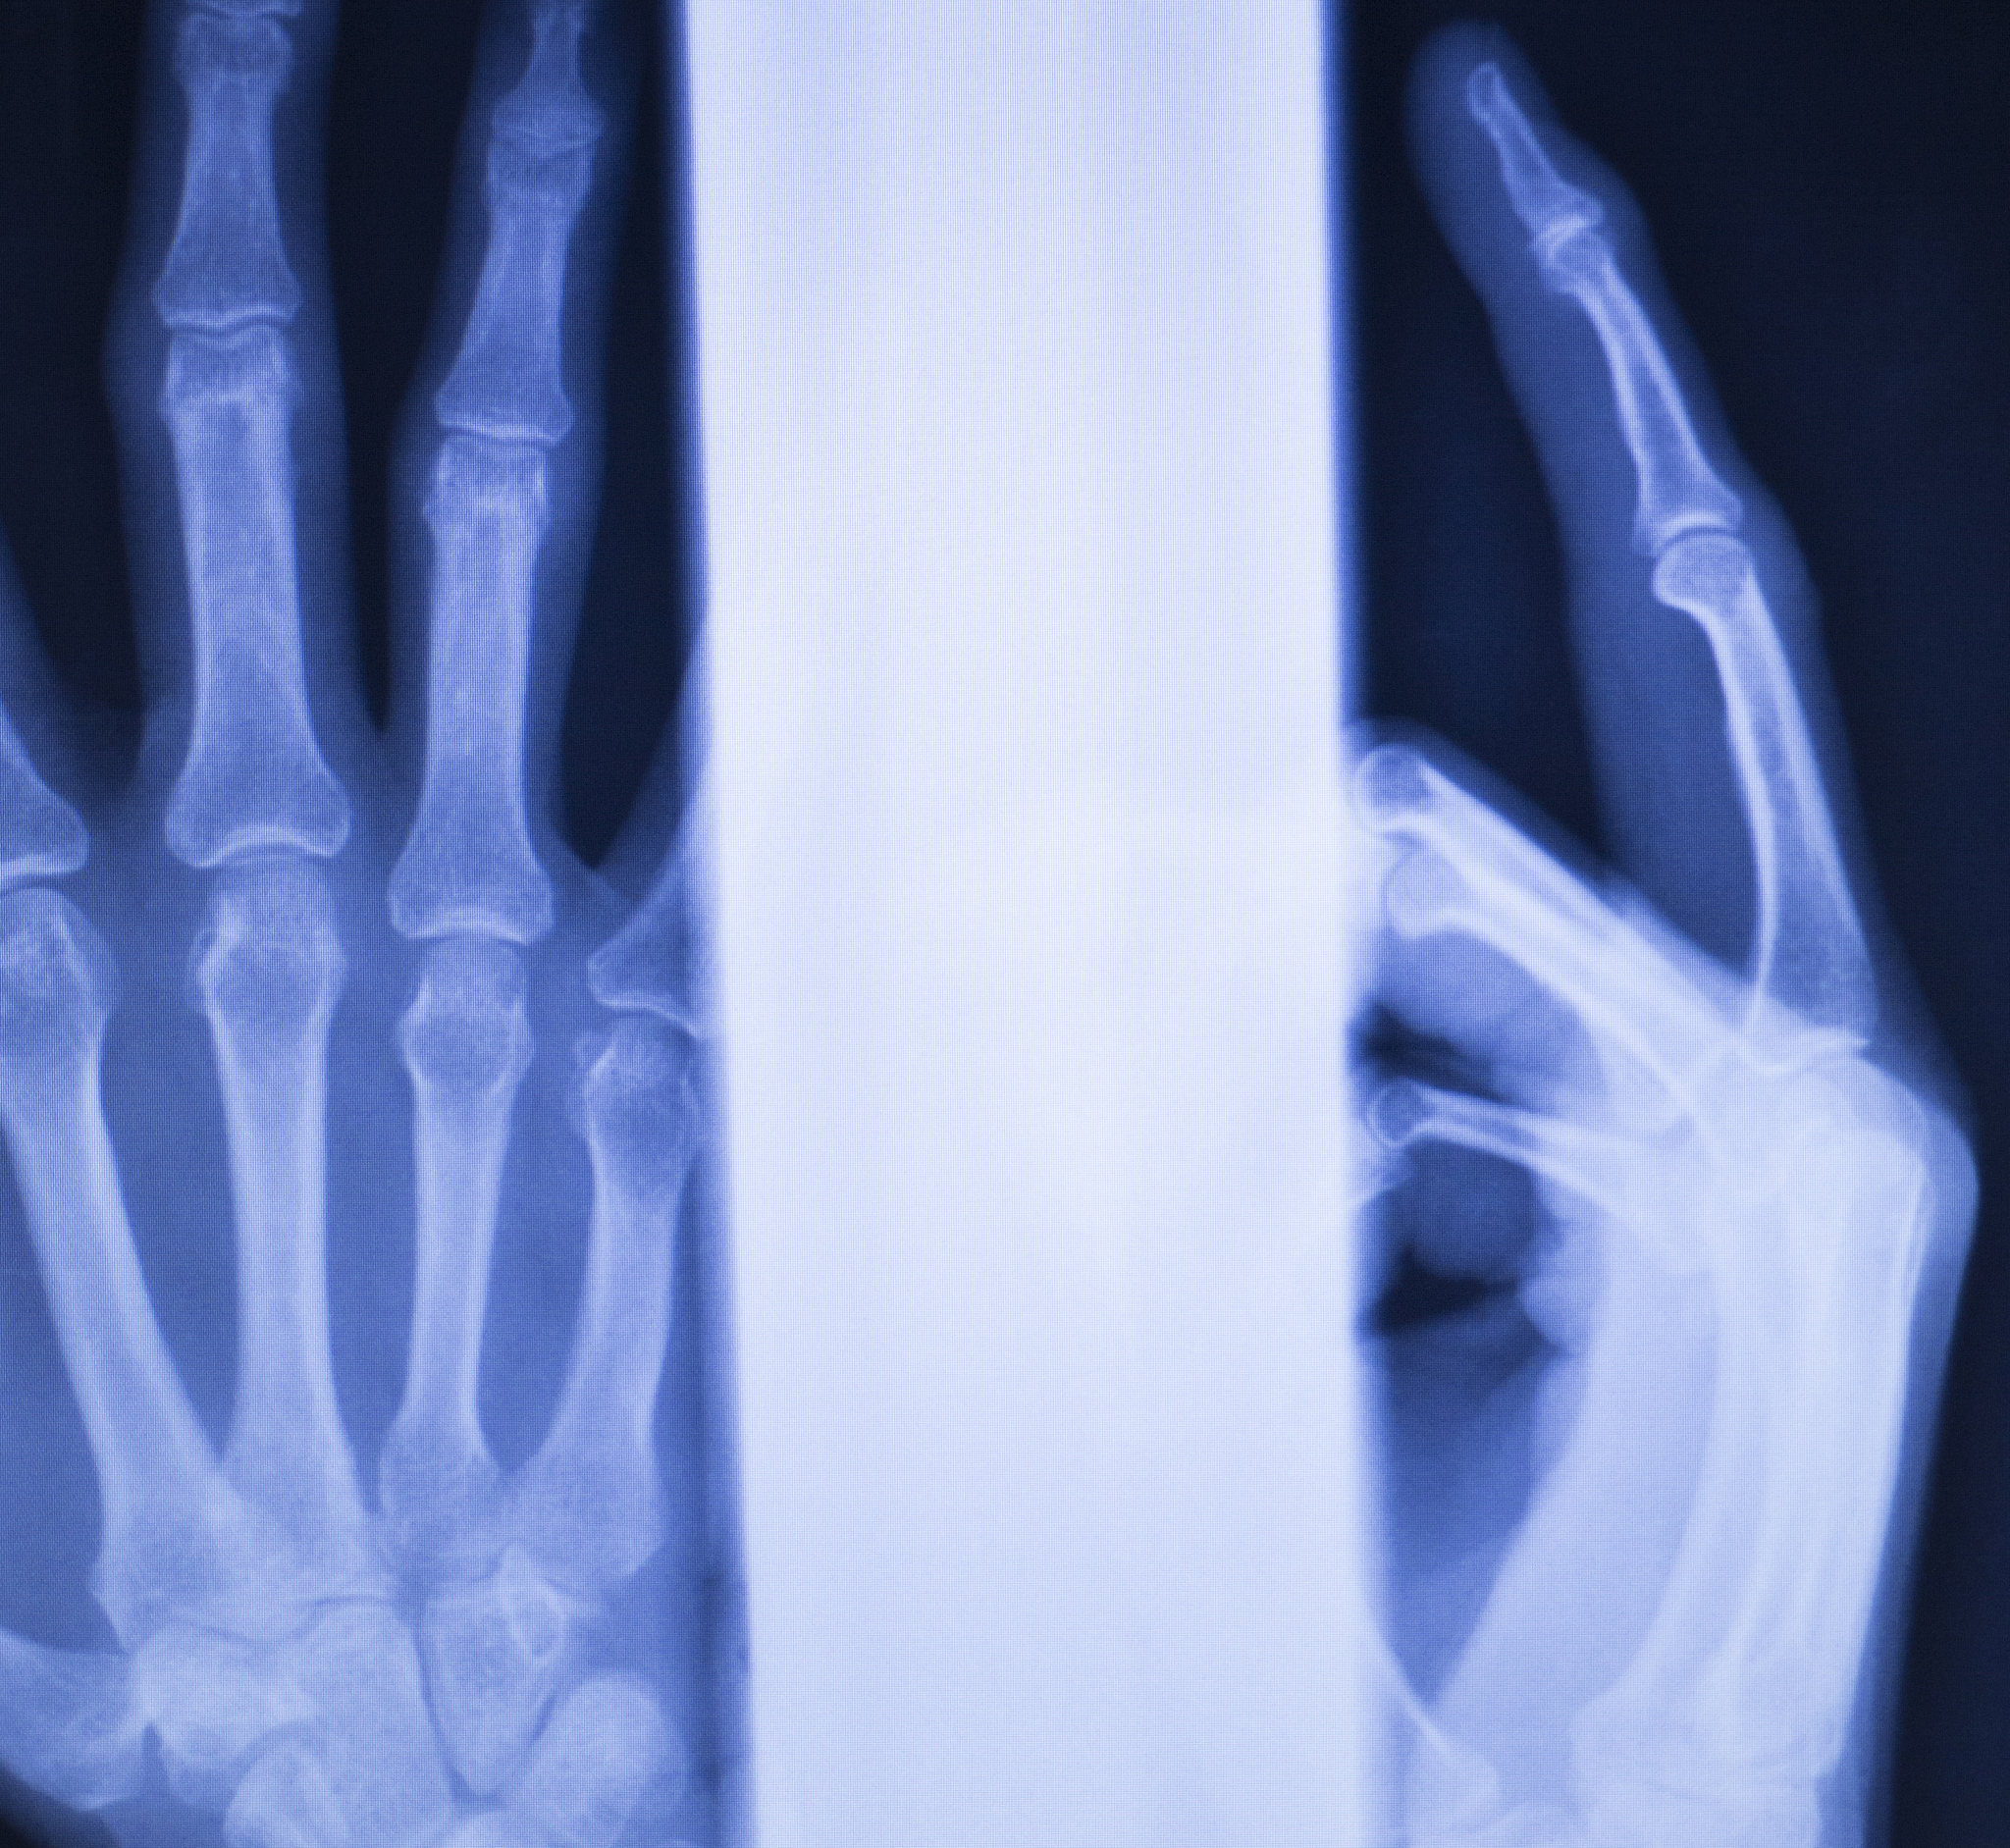

桡骨远端干骺端背侧粉碎性骨折:你需要知道的一切

什么是桡骨远端干骺端背侧粉碎性骨折?

桡骨远端干骺端背侧粉碎性骨折是一种发生在腕关节附近的骨折。它涉及以下几个方面:

• 桡骨远端: 骨折发生在桡骨的远端,靠近手腕的位置。* 干骺端: 骨折发生在干骺端,这是骨骼生长板附近的区域。* 背侧: 骨折线位于桡骨的背侧,也就是手背的那一侧。* 粉碎性: 骨折线多且错乱,导致骨头碎裂成多个部分。